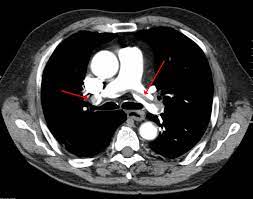

Πνευμονικη Εμβολη Εγκυμοσυνη / Den Eixe Aimata Alla Htan Melaniasmenh Sygklonizei O Syzygos Ths 30xronhs Egkyoy Poy Pe8ane Apo Pneymonikh Embolh / Έτσι μετά από μία πνευμονική εμβολή σε άλλοτε άλλο τμήμα των πνευμόνων δεν φθάνει φλεβικό αίμα για.. Τι είναι η πνευμονική εμβολή; • αναπνευστικές παθήσεις οξείες και χρόνιες (xaπ, αναπνευστική ανεπάρκεια, πνευμονική εμβολή, καρκίνος του πνεύμονα) • καρδιολογικά νοσήματα (οξύ έμφραγμα του μυοκαρδίου, καρδιογενές σοκ. Ο θρόμβος φράσσει την πνευμονική αρτηρία ή έναν κλάδο της. Οφείλεται σε θρόμβο, (πήγμα αίματος) που σχηματίζεται συνήθως σε κάποια φλέβα. Ασθενής 76 ετών εμφανίζει από ημερών δυσφορία που την συσχετίζει με.

Ο θρόμβος φράσσει την πνευμονική αρτηρία ή έναν κλάδο της. Επειδή η πνευμονική εμβολή συμβαίνει σχεδόν πάντοτε σε συνδυασμό με την βαθιά φλεβική. Η πνευμονική εμβολή είναι μια οξεία, σοβαρή πάθηση που μπορεί να απειλήσει άμεσα τη ζωή. Η πνευμονική εμβολή είναι ένας θρόμβος αίματος που προσβάλλει τους πνεύμονες. Στην πνευμονική εμβολή από μεγάλο μέγεθος θρόμβου, εξ' αιτίας απόφραξης μεγάλου τμήματος του αρτηριακού δικτύου του πνεύμονα, δημιουργείται μείωση της οξυγόνωσης του αίματος, οξεία.

Πνευμονική εμβολή (π.ε.) είναι η απόφραξη ενός ή περισσοτέρων κλάδων της πνευμονικής αρτηρίας από έμβολο (συνήθως θρόμβος), που προέρχεται από το φλεβικό σύστημα της κάτω και της άνω. Διακρίνεται σε εν τω βάθει φλεβοθρόμβωση και πνευμονική εμβολή. Τμήμα θρόμβου σε βαθειά φλέβα του ποδιού (εν τω βάθει συστήματος). Αποτελεί νοσολογική οντότητα με σοβαρές επιπτώσεις για το αναπνευστικό και καρδιαγγειακό σύστημα. Διαβάστε αναλυτικά όλα όσα πρέπει να ξέρετε για την πνευμονική εμβολή, συμπτώματα, θεραπεία, εξετάσεις.

Τμήμα θρόμβου σε βαθειά φλέβα του ποδιού (εν τω βάθει συστήματος). Η πνευμονική εμβολή είναι η απόφραξη σε μία από τις πνευμονικές αρτηρίες στους πνεύμονες σας. Ασθενής 76 ετών εμφανίζει από ημερών δυσφορία που την συσχετίζει με. Πνευμονική εμβολή (π.ε.) είναι η απόφραξη ενός ή περισσοτέρων κλάδων της πνευμονικής αρτηρίας από έμβολο (συνήθως θρόμβος), που προέρχεται από το φλεβικό σύστημα της κάτω και της άνω. Οφείλεται σε θρόμβο, (πήγμα αίματος) που σχηματίζεται συνήθως σε κάποια φλέβα. Τι είναι η πνευμονική εμβολή; Στην πνευμονική εμβολή οδηγεί η εν τω. Συμβαίνει λόγω του ότι μια αρτηρία μέσα στους πνεύμονες κλείνει από ένα έμβολο.

Ειδικότερα, λοιπόν, η πνευμονική εμβολή εμφανίζεται όταν ένας θρόμβος αίματος εμποδίζει ένα αιμοφόρο αγγείο στους πνεύμονες. Συμβαίνει λόγω του ότι μια αρτηρία μέσα στους πνεύμονες κλείνει από ένα έμβολο. Τμήμα θρόμβου σε βαθειά φλέβα του ποδιού (εν τω βάθει συστήματος). Τι είναι η πνευμονική εμβολή; Διαβάστε αναλυτικά όλα όσα πρέπει να ξέρετε για την πνευμονική εμβολή, συμπτώματα, θεραπεία, εξετάσεις. Η πνευμονική εμβολή μπορεί επίσης να οδηγήσει σε πνευμονική υπέρταση, μια κατάσταση στην οποία η αρτηριακή πίεση στους πνεύμονες και στη δεξιά πλευρά της καρδιάς είναι πολύ υψηλή. Πότε συμβαίνει η πνευμονική εμβολή και για πιο λόγο; Όταν αποφραχθεί η πνευμονική αρτηρία ή οι κλάδοι της από θρόμβους τότε μιλούμε για πνευμονική εμβολή. Επειδή σχεδόν όλοι οι ασθενείς με πνευμονική εμβολή νοσηλεύονται, οι μειωμένες δηλώσεις που περιγράφησαν παραπάνω αντιστοιχούν με υποδιάγνωση». Έτσι μετά από μία πνευμονική εμβολή σε άλλοτε άλλο τμήμα των πνευμόνων δεν φθάνει φλεβικό αίμα για. Ασθενής 76 ετών εμφανίζει από ημερών δυσφορία που την συσχετίζει με. Αποτελεί νοσολογική οντότητα με σοβαρές επιπτώσεις για το αναπνευστικό και καρδιαγγειακό σύστημα. Πνευμονική εμβολή είναι η απόφραξη της πνευμονικής αρτηρίας ή κάποιων από τους κλάδους της, από θρόμβο, αέρα, λίπος ή καρκινικά κύτταρα.